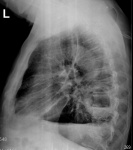

Пациент доставлен скорой помощью ночью. Абсцесс левого лёгкого. (++)

Пациент доставлен ночью скорой помощью в приёмное отделение в довольно тяжелом состоянии. Отмечается повышение температуры до 39 градусов, кашель со скудной мокротой, недомогание, выраженную потливость ночью.

Накануне пациенту (в другом районе) была сделана рентгенограмма ОГК в прямой проекции.

Какие мнения будут у уважаемых коллег по имеющейся рентгенограмме?

Абсцесс в S6, гидроторакс, междолевой выпот.

Абсцесс накладывается на позвоночник.

Какой диагноз вынес пульмонолог? Мне кажется вопрос по абсцессу не требует уточнения, на границе S6-S10. Более интересна била бы жидкость, как осложнение абсцесса, который в свою очередь может быть тоже вторичным.

Консультатнт ТОЛЬКО ПО РЕНТГЕНОГРАММЕ, ПРОИЗВЕДННОЙ В ПРЯМОЙ ПРОЕКЦИИ, вынес диагноз - абсцесс...

Не поспешно ли. На боковой абсцесс должен быть виден яснее, если он абсцесс.

Абсцесс-создание не бестелесное . Сбоку должен быть виден не жуже, чем на прямой. А в этом боку-только погадать о нём.

Хоть побейте меня об этот боковой. Не вижу в нём абсцесса. Даже не знаю чтобы делал в такой ситуации, скопил бы или резал.

Ещё раз пересмотрел и в абсцессе сильно засомневался. Не плеврит ли в междолёвке, хитрый такой с уровнем. Ну не таким должен быть абсцесс.

Рентген-контроль через 1 неделю.

Сейчас во всей красе абсцесс.

Динамика положительная. Абсцесс. Вплевральные спайки.